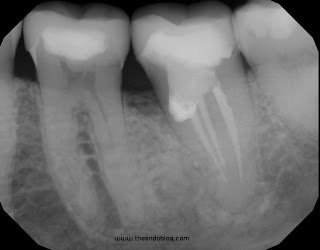

Root Canal on a C-shaped, 2nd molar, through a crown with mild angulation and calcified canals makes this root canal a “HIGH DIFFICULTY” level.  The clinician performing this treatment had challenges due to these issues.  Access was difficult, interpreting the c-shaped canal was difficult and C-shaped canal all led to the mesial perforation.  The calcified canals also made it difficult to instrument/fill to the apex.  The perforation was improperly managed by sealing with gutta percha and patient was not informed of the complication.